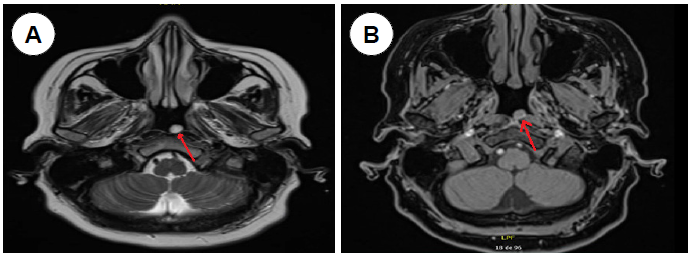

Mujer de 48 años de edad, con historia de tres meses de inestabilidad, en especial al realizar movimientos, y concomitantemente dolor y rigidez cervical. El examen clínico otorrinolaringológico fue normal, la audiometría mostró normoacusia y los exámenes vestibulares normales. Se solicitó resonancia magnética de fosa posterior con contraste encontrándose una lesión nodular en la nasofaringe de 0,7 cm de diámetro en T1 y T2, (figura 1A y B) que no varió con el contraste no afectando a estructuras óseas, sugerente de quiste de Thornwaldt (figura 2). Se realizó endoscopia nasal observándose una lesión regular lisa, de aspecto quístico en la nasofaringe (figura 3). Se decidió realizar marsupialización del quiste bajo abordaje endoscópico transnasal, se retiró los bordes y se cauterizó con electrocauterio, sin mayor complicación; el informe anatomopatológico descartó lesiones malignas informando solo tejido inflamatorio. El caso fue catalogado como quiste de Thornwaldt. La paciente presentó mejoría de dolor y rigidez cervical, aunque la inestabilidad se mantiene.

El diagnostico está basado en la endoscopia nasal y en imágenes, en muchos casos se encuentra de forma casual. En la endoscopia nasal, se observa una lesión redonda, de superficie lisa, de aspecto quístico (5,7). La tomografía, así como la resonancia son de gran utilidad, pero para algunos autores la resonancia se considera como el gold estándar para el diagnóstico, ya que se puede apreciar la lesión, la misma que resalta con gran intensidad tanto en T1 y T2, por el contenido proteico y hemorragias que presenta el quiste aun sin contraste con gadolinio (4,6,9,10).